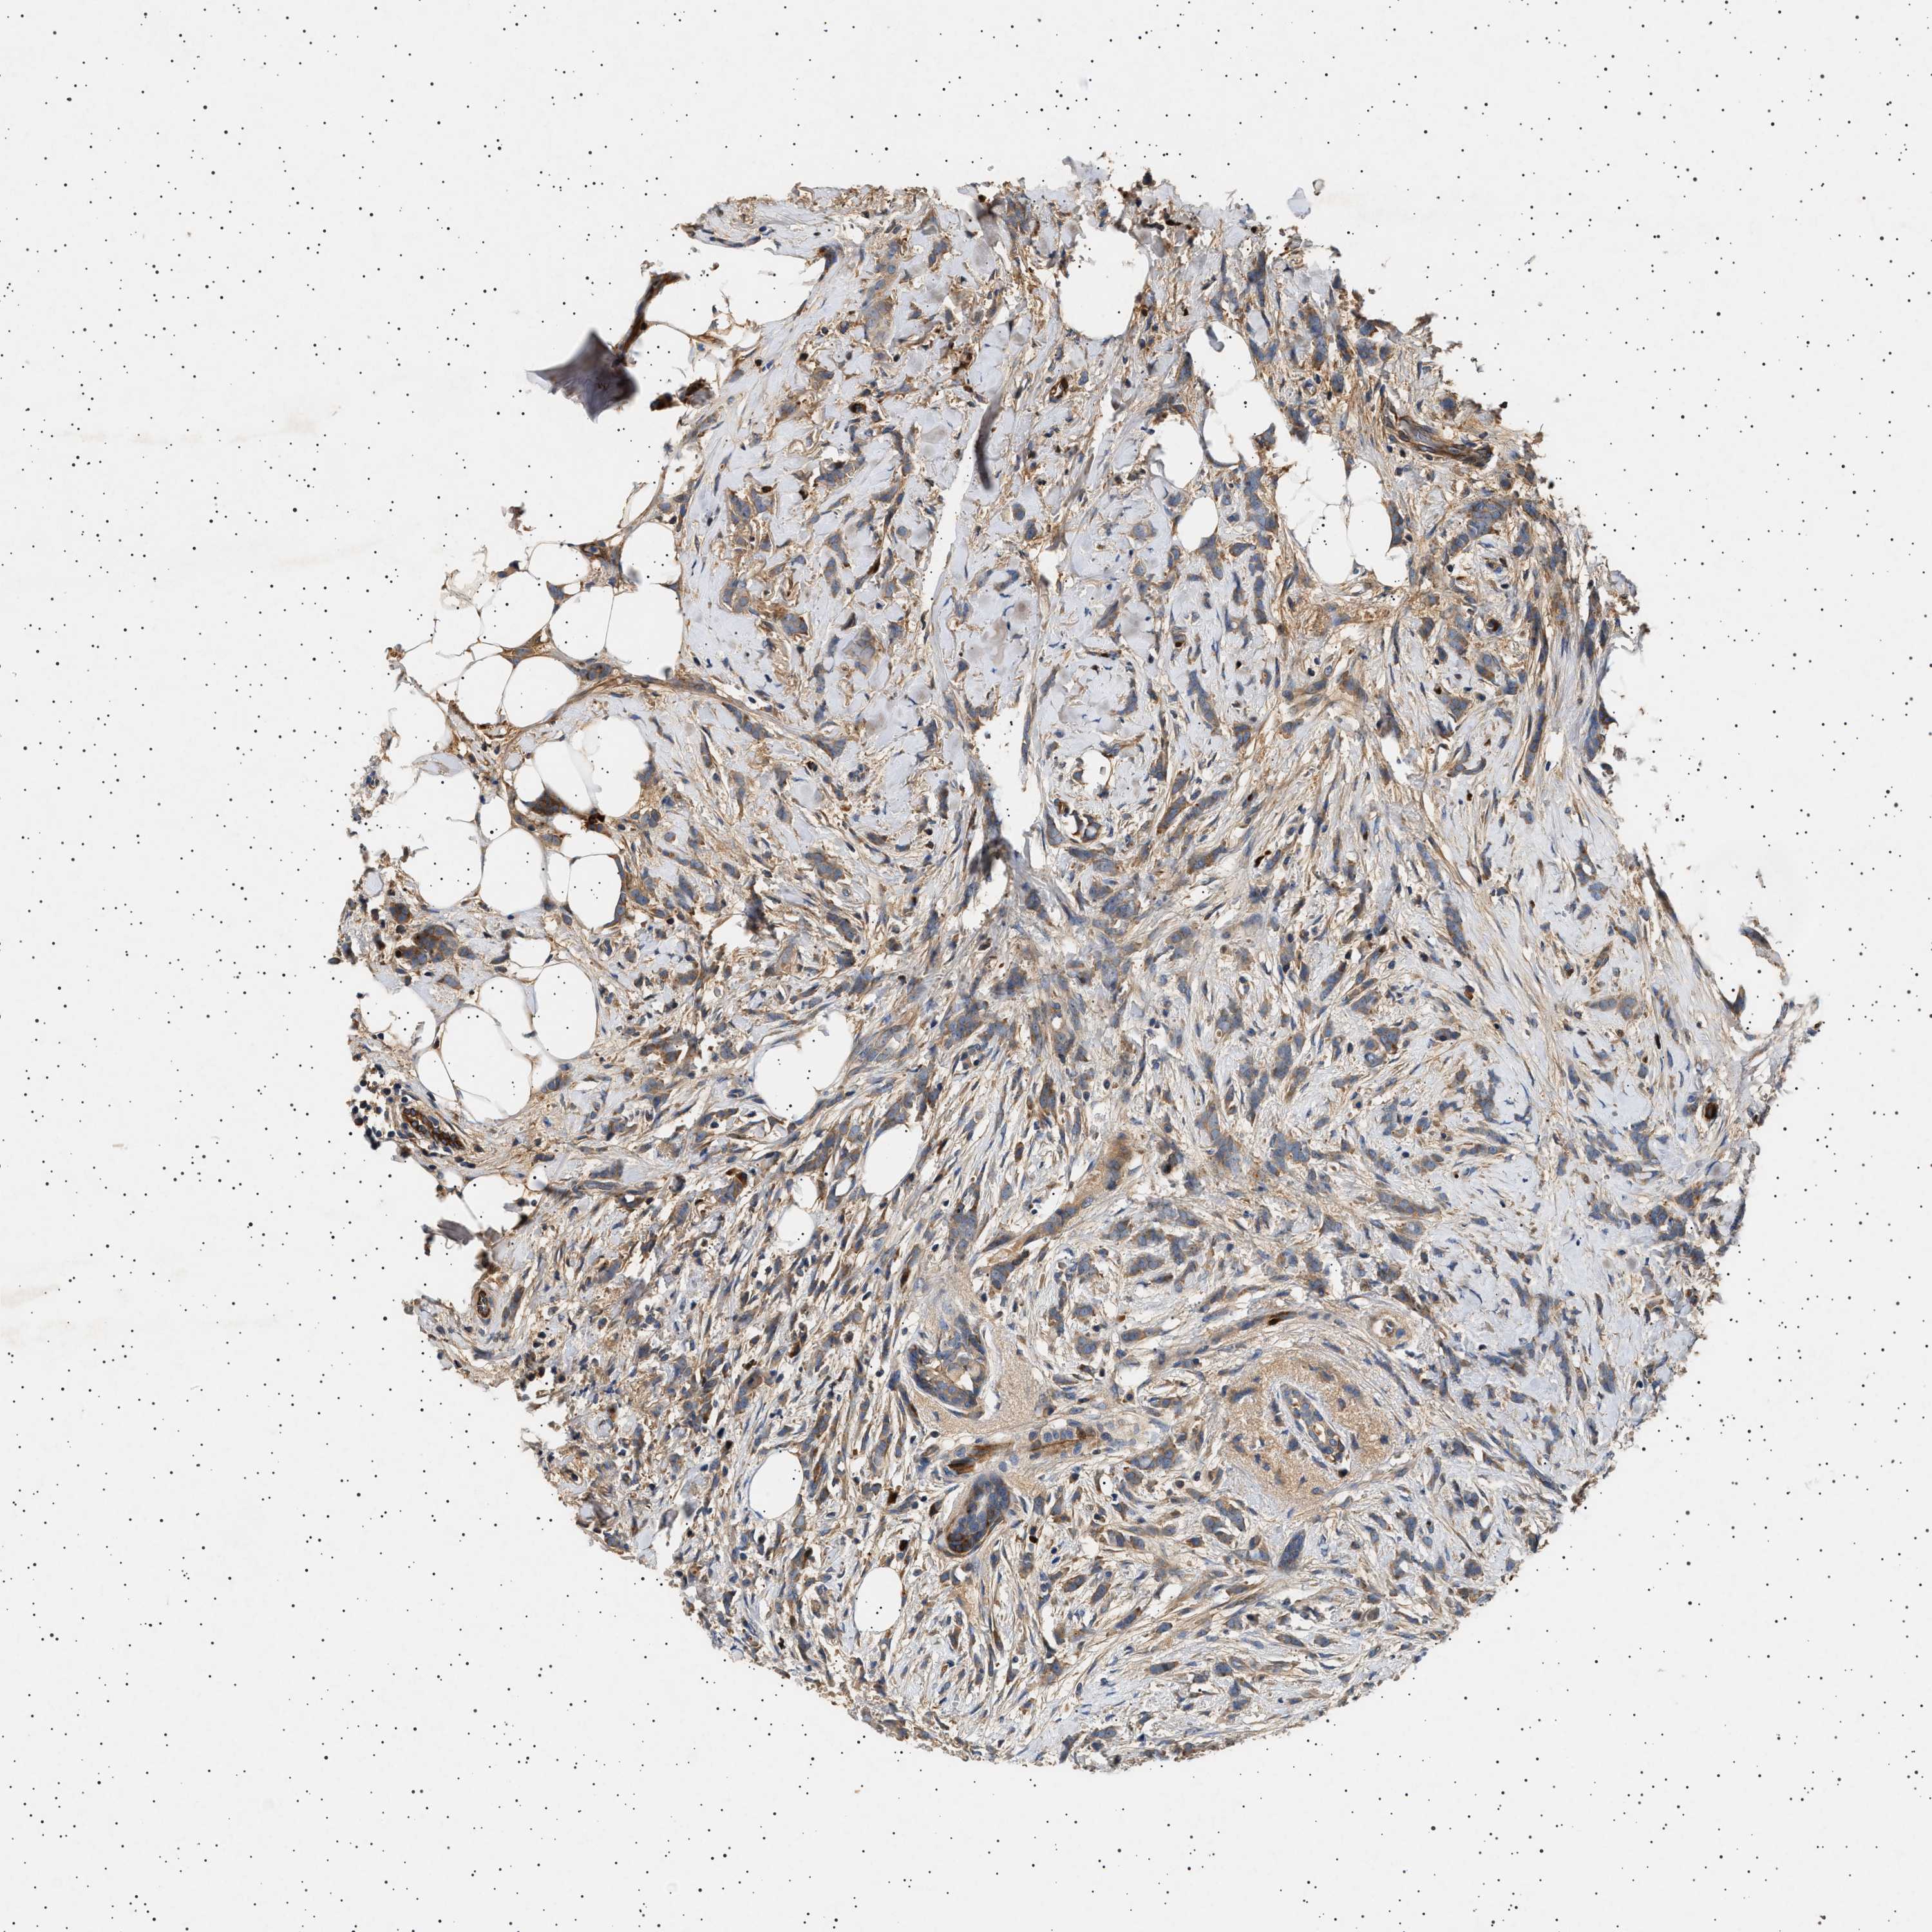

CANCER BREAST CANCER Show tissue menu

BRCA TCGA BRCA VALIDATION PROTEIN EXPRESSION

ANTIBODIES

AND

VALIDATION